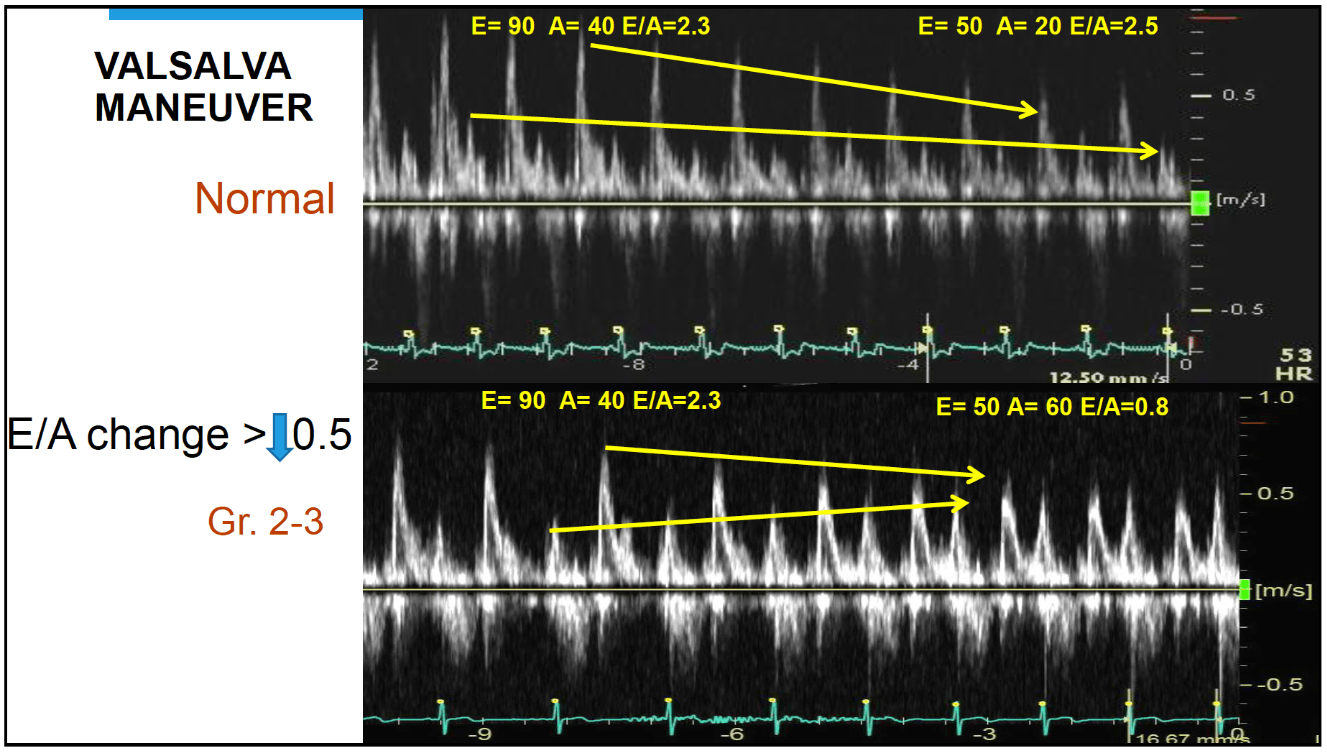

The diastolic function when there is no significant change in E/A with Valsalva maneuver.

What is normal diastolic function?